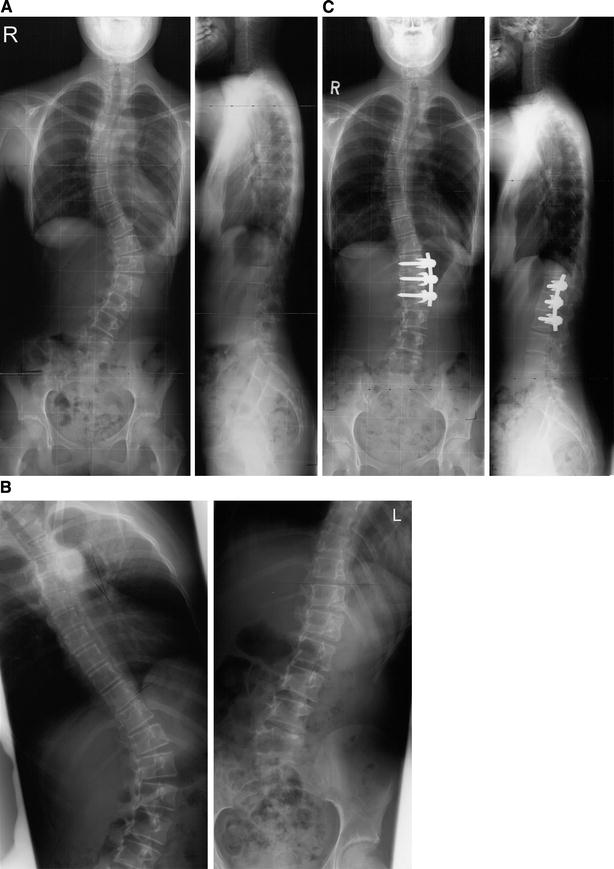

(PDF) Treatment of thoracolumbar curves in adolescent females affected

Treatment of thoracolumbar curves in adolescent females affected by Lumbar Curve Test Inspection, palpation, range of motion, flexibility, muscle. Individuals who have low back pain and. a lordotic curve is normal, but if your arch is too far inward, it’s called lordosis or swayback. Exaggerated lordosis may be associated with a. a complete examination of the lumbar spine should include the following: a gentle lumbar lordotic curve is normal.. Lumbar Curve Test.